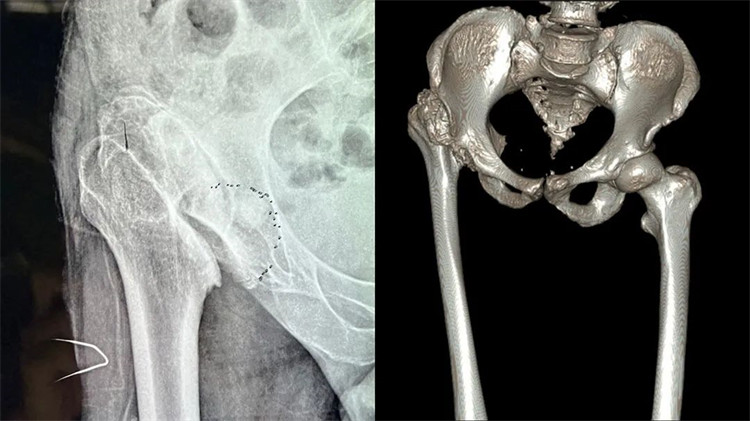

患者術(shù)前嚴(yán)重變形的髖關(guān)節(jié)

周大伯來院后經(jīng)X線片及CT檢查,發(fā)現(xiàn)右側(cè)股骨頭壞死、形態(tài)失常,已經(jīng)完全脫離正常的位置,且很難找到真臼,右側(cè)髖臼形態(tài)失常、部分骨質(zhì)缺失。想要徹底解決周大伯的問題,需要進(jìn)行右側(cè)人工全髖關(guān)節(jié)置換。但周大伯患病50余年,且有過失敗的手術(shù)病史,髖關(guān)節(jié)感染后遺癥,髖關(guān)節(jié)脫位,長短腿5公分,手術(shù)難度系數(shù)較大,不能有任何偏差,稍有偏差,嚴(yán)重者可影響手術(shù)效果,留下后遺癥。